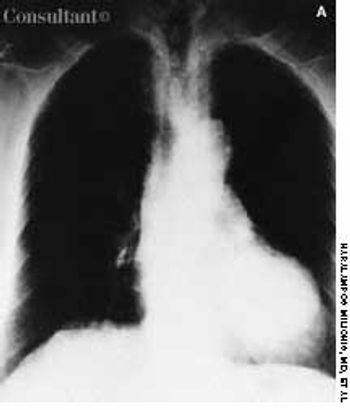

During investigation of a long-standing iron-deficiency anemia, a 67-year-old woman was found to have cecal colon cancer, Duke's stage B. A right hemicolectomy was performed at that time, and she had periodic follow-up examinations. Four years later, during a routine outpatient visit, her carcinoembryonic antigen (CEA) serum level was found to be 27.7 ng/mL (upper normal limit, 5 ng/mL). Four months earlier, her CEA level had been normal.